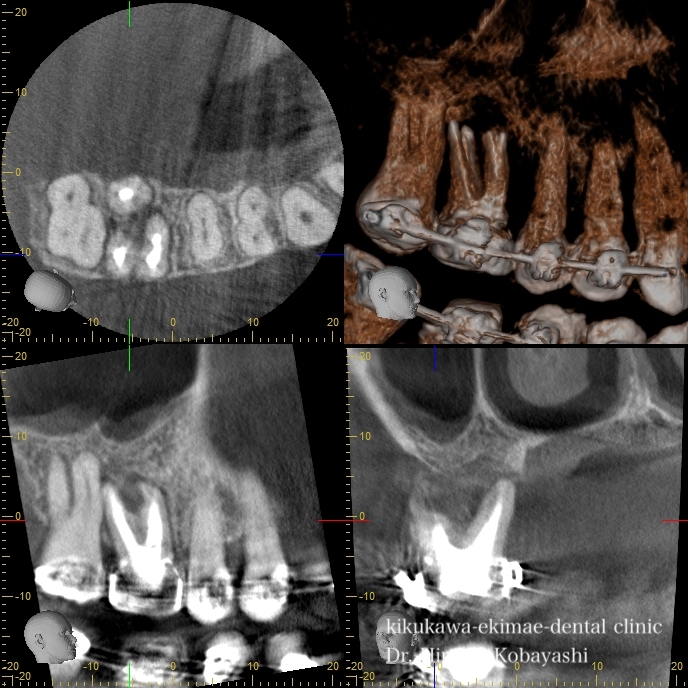

歯茎からオデキが出来たと来院されました。 CT撮影を行いますと、根の感染が見られました。感染の長期の放置により骨が溶けており、歯の保存が難しそうな状況でした。痛みもなく、特に生活に支障はありませんが、刻一刻と早期に歯を失う方向に進んでいます。おそらく、数年このままですと痛みもなくある日、ぐらぐらし、抜け落ちていたでしょう お話し合いの上、精密根管治療にて歯の保存を希望されましたので、治療を開始しました。   時間をかけ、顕微鏡を使用し感染の除去を行なっていきます。過去に根の処置を行なった時に入れたであろう薬剤や膿や出血が出てきます。 2時間程度のアポイントを3回お取りし、精密根管治療が完了しました。 オデキはなくなり、無事歯を残す事が出来ました。   CTにて経過を見ますと骨の再生が起きています 約6ヶ月〜程度かけて骨の再生が起こります。 リスク 極端に硬いものを噛むとかける可能性があります。 各種治療費はこちらから